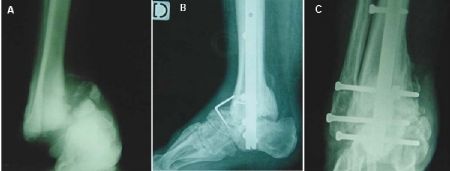

Technique Comment je fais une arthrodèse tibio-talo-calcanéenne par clou rétrograde ? , Olivier Laffenêtre Groupe de Recherche et d'Etude en Chirurgie Mini-Invasive du Pied, 33700 Merignac, France , GD. Solofomalala CHU Pellegrin – Bordeaux – France , L. Villet CHU Pellegrin – Bordeaux – France , Dominique Chauveaux CHU Pellegrin, Bordeaux, France N°166 - Août 2007 ● 16 min de lecture